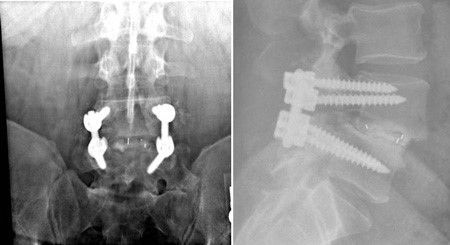

x-rays of TLIF procedure

In these front and side views of a TLIF procedure, note the screws in the back of the vertebrae. The cage can only be seen by the white metal markers. Bone graft is in the disk space inside and around the cage.